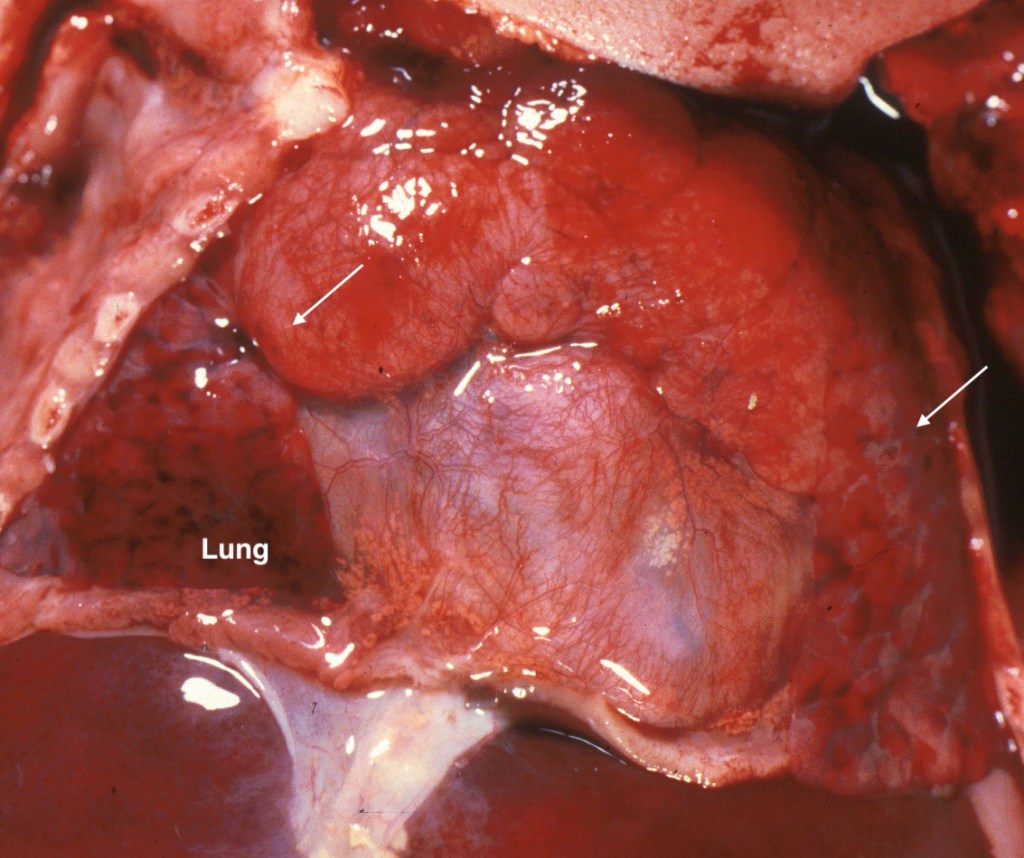

3. Thymic hemorrhages:

Thymic petechiae are a commonly encountered lesion in stillbirth. They appear as small pinpoint dots of red, or as larger confluent pattern of small hemorrhages. If due to gasping, they should not be in the cervical portions of the gland. (Fig 5, 6) Larger hemorrhages occur only rarely. One such case was associated with massive thymic and intracerebral hemorrhage [4]. The authors did not comment on any possible platelet PL1 antigen sensitization.